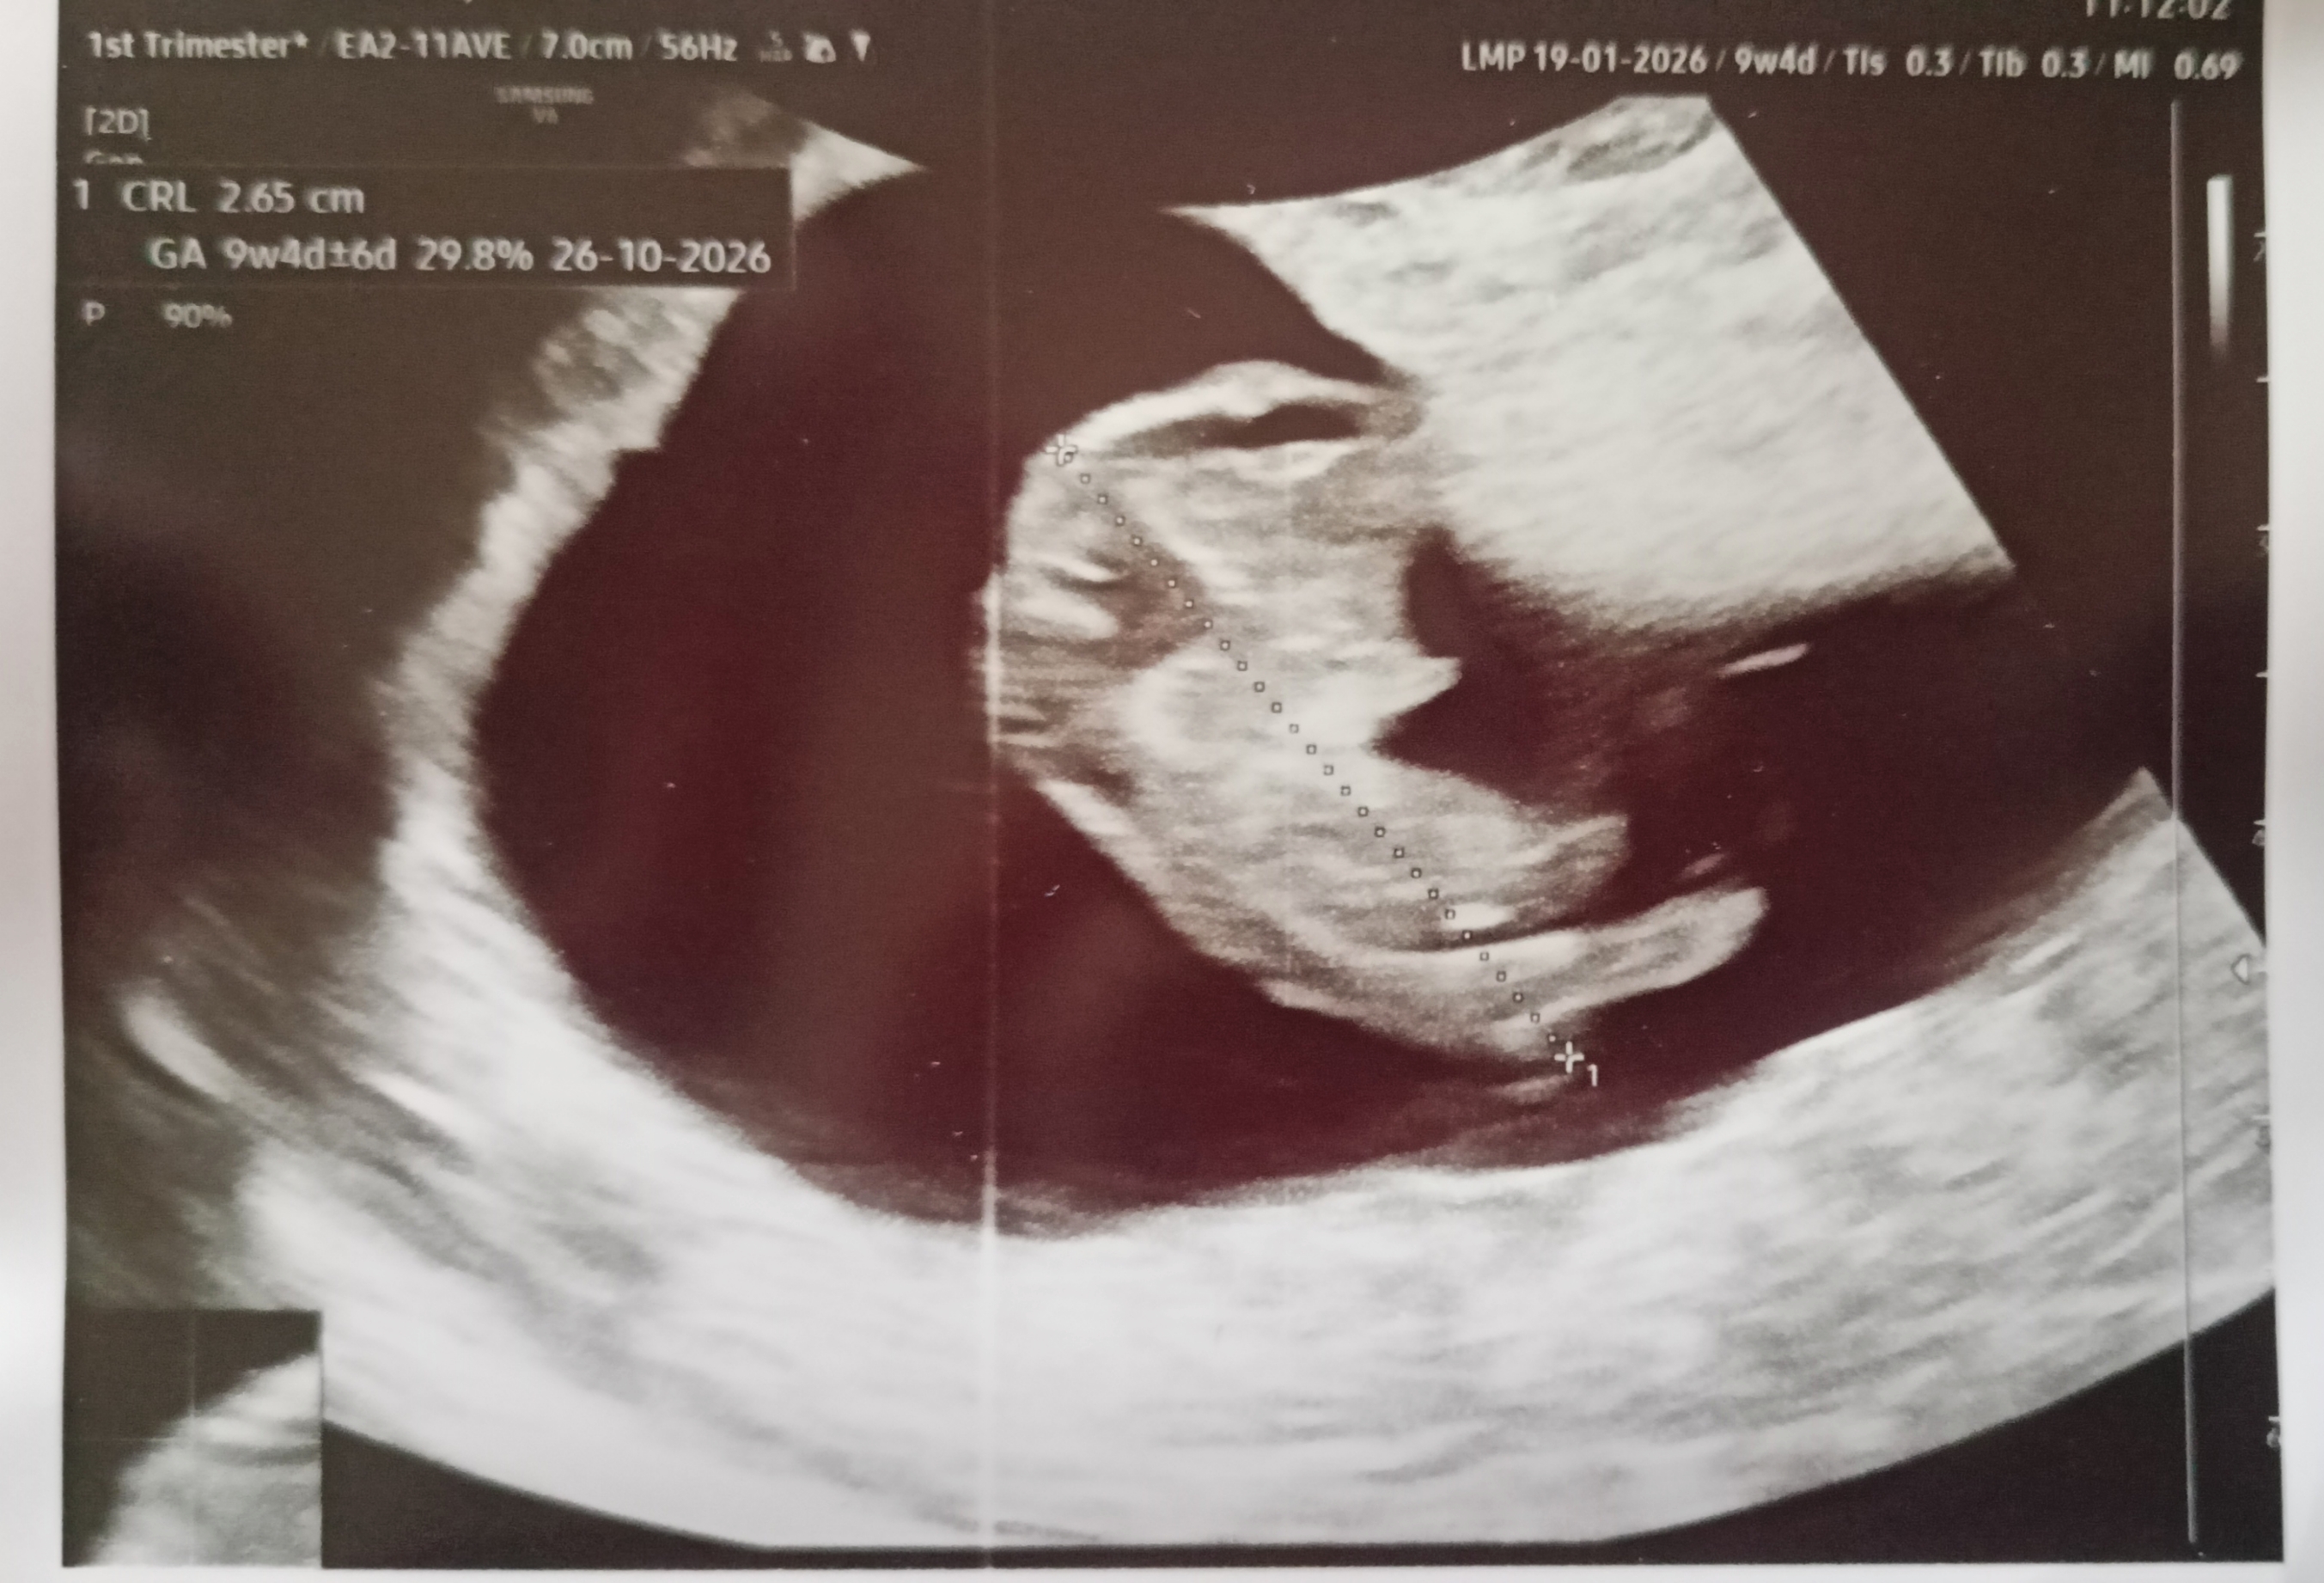

Z dzidzią wszystko dobrze 😍

Ma już 2,65 cm

https://zapodaj.net/plik-EX2OoqfWpA

Kolejna wizyta na prenatalnych 21.04. Lekarka powiedziała, żebym prywatnie na razie się nie umawiała skoro będziemy się widzieć, ustalimy na prenatalnych. Ale pewnie jakoś 4 tygodnie po prenatalnych będzie kolejna wizyta.Wiadomość wyedytowana przez autora: Dzisiaj, 12:14